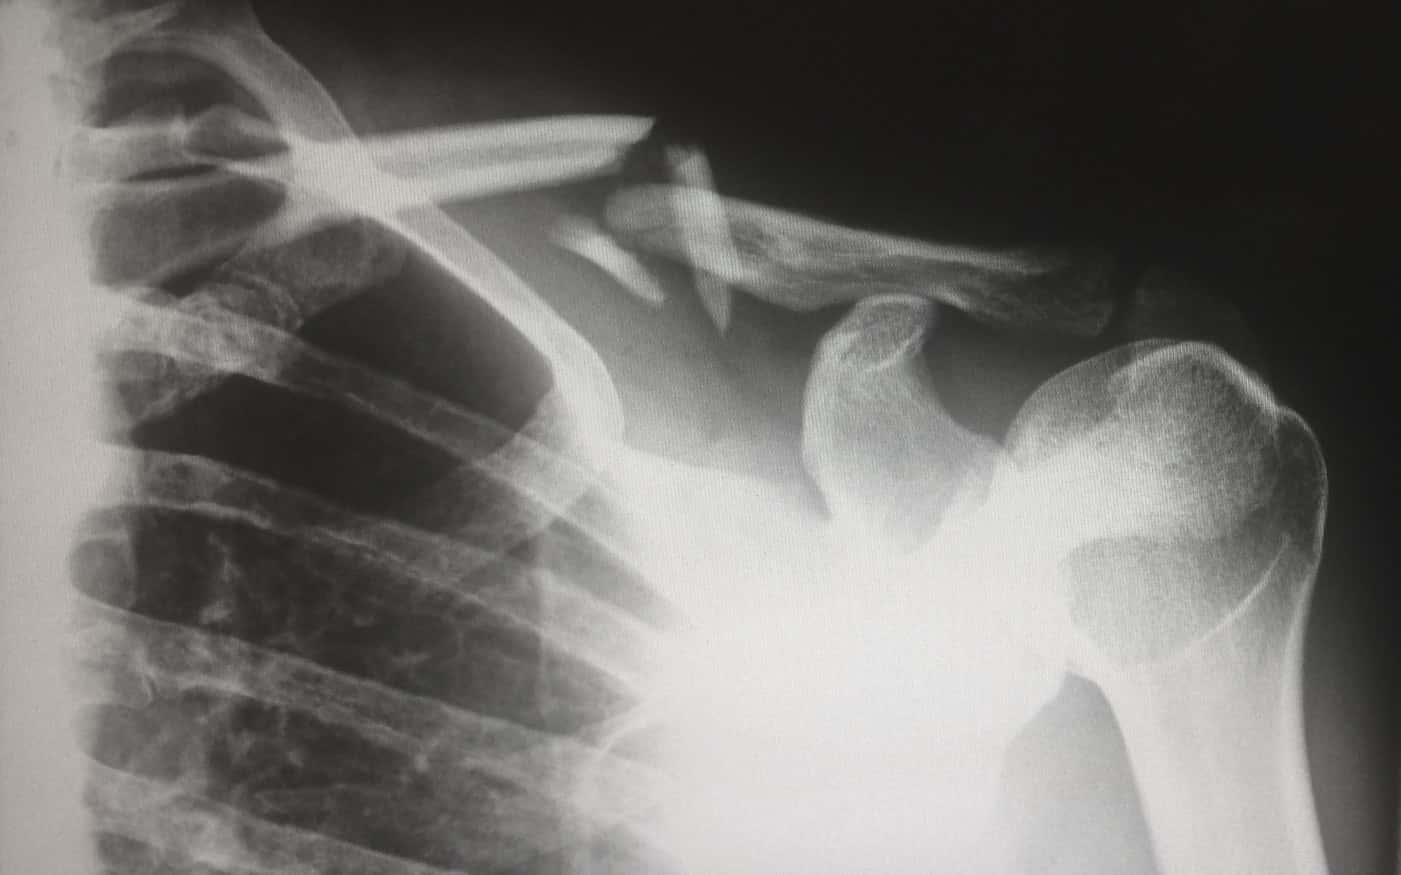

#26 Unlucky Fall

Not a doctor but a medical technician. This definitely isn’t as graphic as some of the other stories but the interesting thing is that it happened yesterday. We had a patient who was on a ladder (I believe he was trying to change a light bulb) and he fell off the ladder. He broke every single one of his ribs and gave himself a hemothorax (that’s when blood gets into the pleural space making it difficult to breathe). He was rather young too, the 40s to 50s.